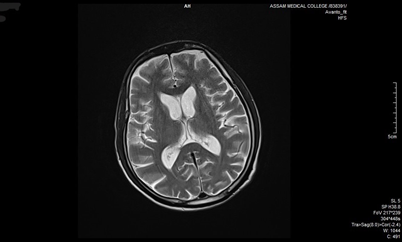

Skull bone marrow plays a critical role in central nervous system (CNS) immunity by housing specialized immune cells that interact directly with cerebrospinal fluid (CSF), influencing neuroinflammation and neurodegeneration. Unlike peripheral marrow, skull marrow uniquely contributes to brain immune responses. Non-invasive imaging techniques such as TSPO-PET show strong potential for detecting skull marrow activity in conditions like Alzheimer’s and multiple sclerosis, offering an alternative to invasive bone marrow biopsies (Table 3). Additionally, intracalvarial drug delivery, which bypasses the blood-brain barrier, significantly enhances therapeutic delivery to the brain. This emerging approach holds promise for improving treatment outcomes in CNS disorders and warrants further investigation.